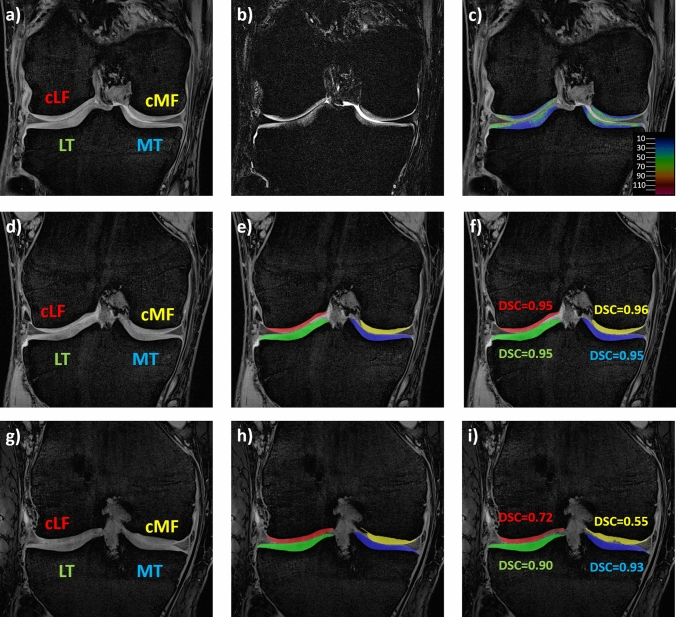

Objective: To clinically validate a fully automated cartilage segmentation technique from quantitative double-echo steady-state (qDESS) MRI supporting simultaneous estimation of cartilage T2 and morphology. Here, we test whether laminar (superficial and deep layer) T2 results from convolutional neural network (CNN) segmentations are consistent with those from manual expert segmentations.

Materials and methods: The 3D qDESS sequence was acquired using 3 T MRI (resolution: 0.3125 × 0.3125x1.5 mm) in both knees of 37 subjects with unilateral anterior cruciate ligament (ACL) injury and 48 uninjured controls. Automated femorotibial cartilage (FTJ) segmentation was based on a 2D U-Net. Laminar T2 and cartilage thickness across the FTJ) were compared between ACL-injured and contralateral knees, and between ACL-injured and control knees. Effect sizes of these differences were measured using non-parametric Cohen's d (dn-p).

Result: Significant differences were observed only in deep T2, with longer T2 in ACL-injured knees than in contralateral and healthy control knees in most of the comparisons and with similar effect sizes for automated and manual segmentations (range dn-p automated/manual: 0.58-1.04/0.58-0.74). No significant differences were observed in superficial T2 or cartilage thickness.

Discussion: Fully-automated, CNN-based analysis showed similar sensitivity to differences in laminar cartilage T2 as manual segmentation, allowing automated qDESS-analyses to be applied to larger datasets.